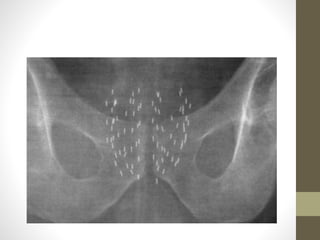

• Plain X ray to evaluate symmetry & spacing

LDR procedure • Patientis placed under spinal or general anesthetia • Supine in lithotomy position & catheterisation • Contrast is placed in the bladder • Applicator template is secured to TRUS apparatus • Reference plane 0.0 (base of the prostate) • Needles are inserted • USG axial & sagittal views will guide the placement of the needle • Seeds are dropped within the prostate • Lineal alignment & spacing • Plain X ray to evaluate symmetry & spacing • Bladder irrigation & cystoscopy to evacuate migrated seeds & clots